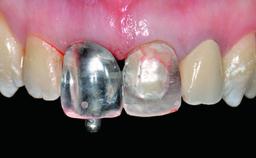

Replacement of a Missing Upper Left Central Incisor: Late Placement of an RC Bone Level Implant, CAD/CAM Zirconia Abutment

Abutment Type CAD/CAM

Prosthesis Type FDP